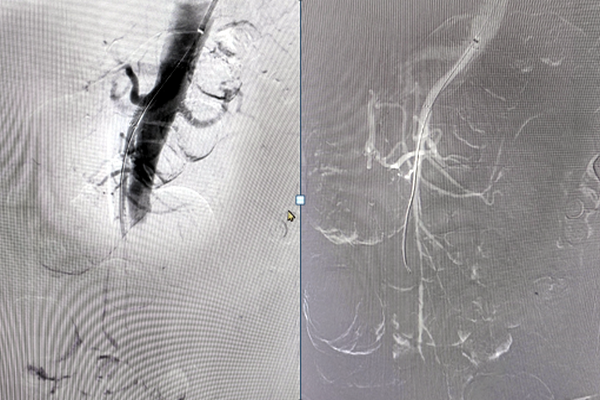

穿刺左侧肱动脉,入5F血管鞘,单弯导管配合超滑导丝超选择进入肠系膜上动脉,造影可见肠系膜上动脉主干血栓形成,更换8F长鞘至肠系膜上动脉开口处,入Indigo机械血栓抽吸系统,反复吸栓3次后,造影见肠系膜上动脉主干近端明显狭窄,后于狭窄处植入VBHR06050W覆膜支架系统,再次造影见肠系膜上动脉血流通畅。长鞘入腹主动脉远端,造影见左侧髂动脉血栓形成,入Indigo机械血栓抽吸系统,反复吸栓后,局部可见明显狭窄,于狭窄处给予球囊扩张后支架植入,造影见髂动脉血流通畅,术毕。郝大爷术后腹痛明显缓解,左下肢疼痛症状消失、皮温明显升高,现已康复出院。

术中造影